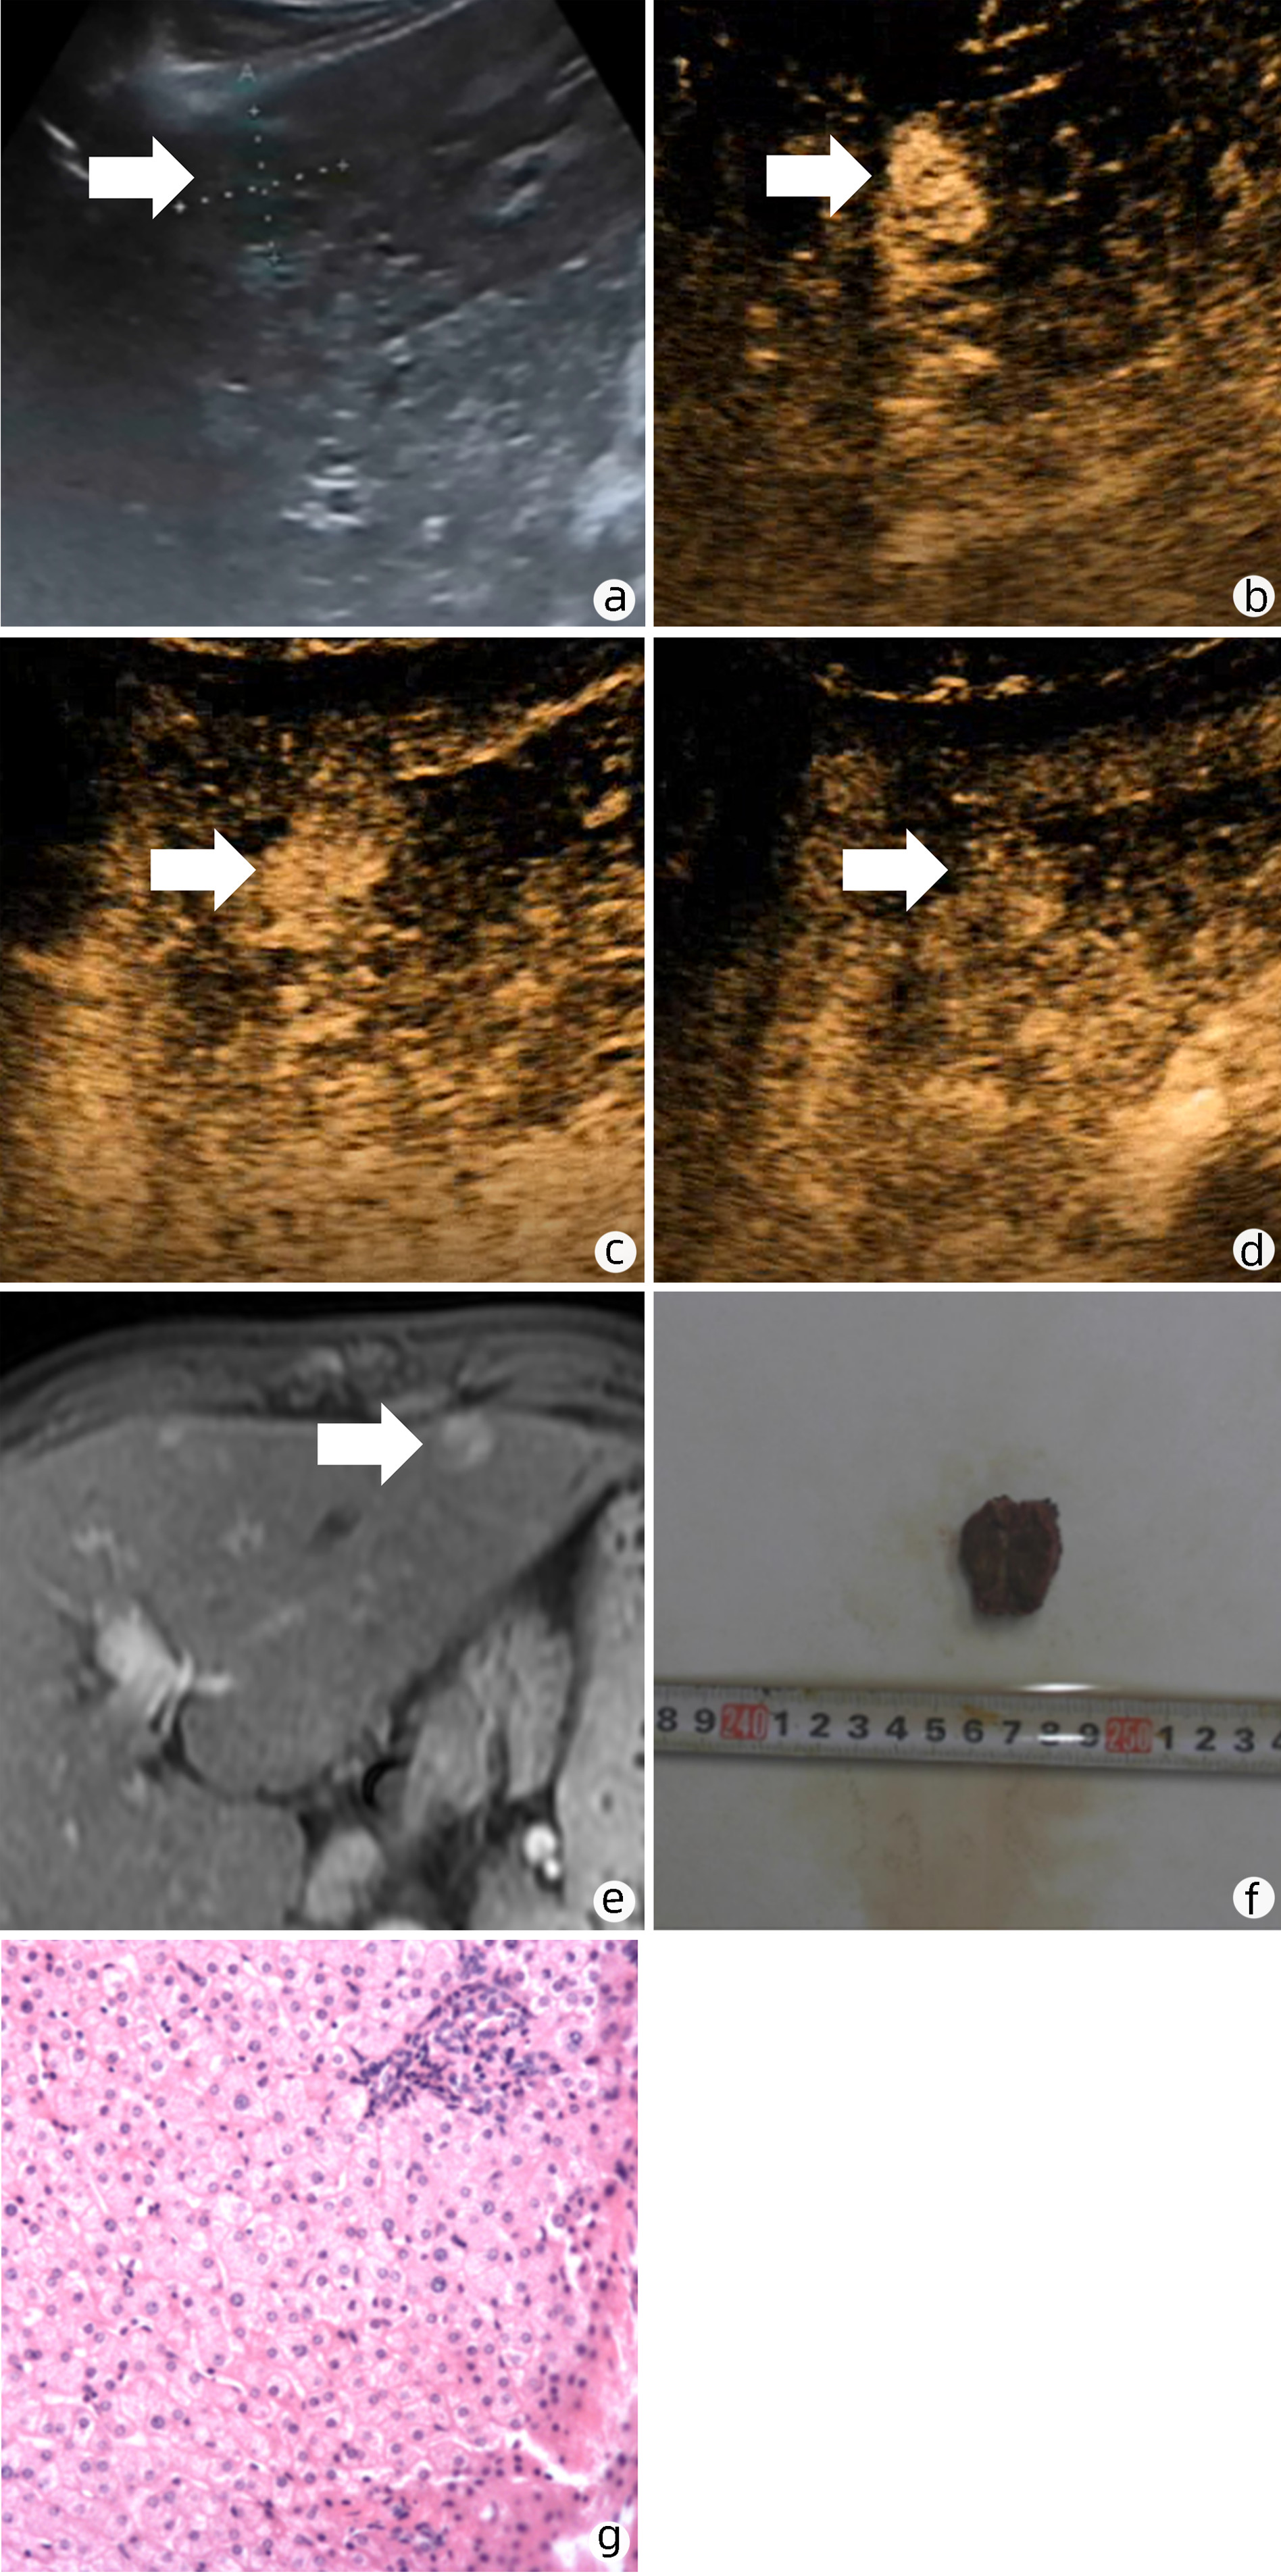

Primary mucoepidermoid carcinoma of the liver: A case report and literature review

Junjie WANG, Cheng CHEN, Yakun WU

2023, 39(1): 152-155. DOI: 10.3969/j.issn.1001-5256.2023.01.023

Abstract(2137) HTML (1487) PDF (3007KB)(131)

Abstract: